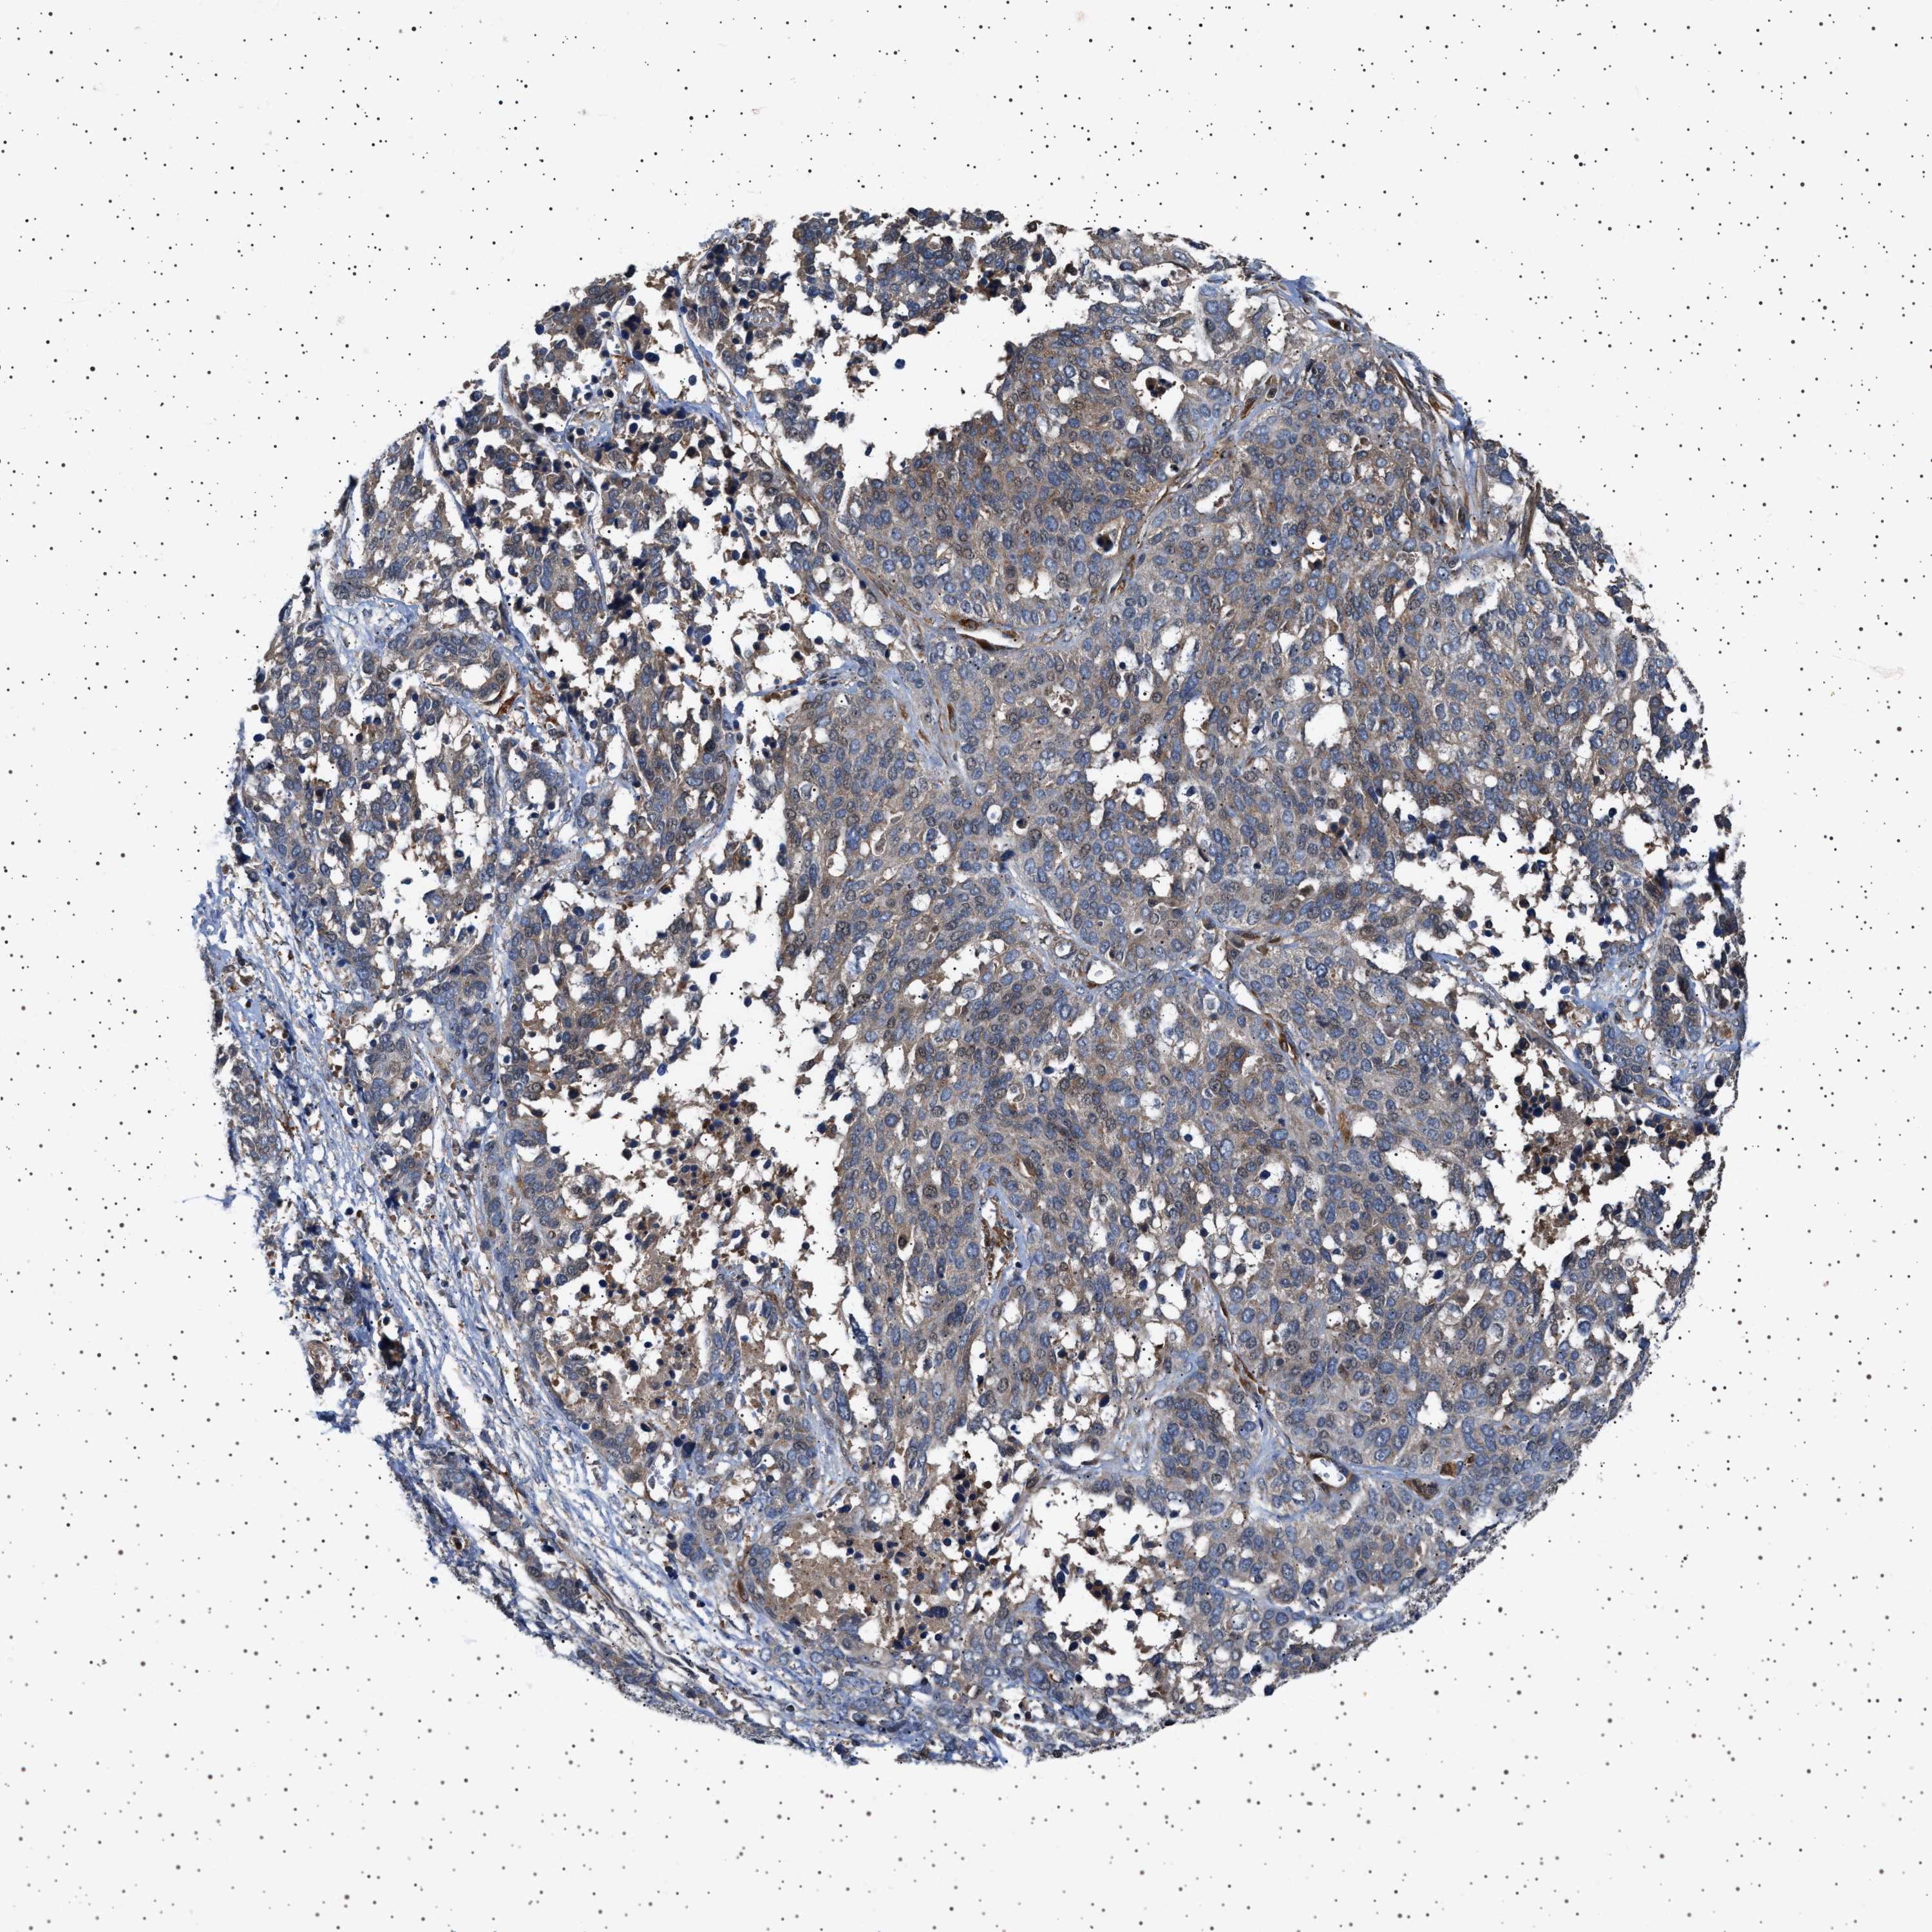

OVARIAN CANCER - Protein expressioni

A mouse-over function shows sample information and annotation data. Click on an image to view it in a full screen mode. Samples can be filtered based on level of antibody staining by selecting one or several of the following categories: high, medium, low and not detected. The assay and annotation is described here.

Note that samples used for immunohistochemistry by the Human Protein Atlas do not correspond to samples in the TCGA dataset.

Antibody stainingi

Antibody staining in the annotated cell types in the current human tissue is reported as not detected, low, medium, or high, based on conventional immunohistochemistry profiling in selected tissues. This score is based on the combination of the staining intensity and fraction of stained cells.

Each image is clickable and will lead to virtual microscopy that enables deeper exploration of all samples and also displays staining intensity scores, fraction scores and subcellular localization as well as patient and tissue information for each sample.

Antibody HPA020870

Antibody CAB010890

Cystadenocarcinoma, serous, NOS